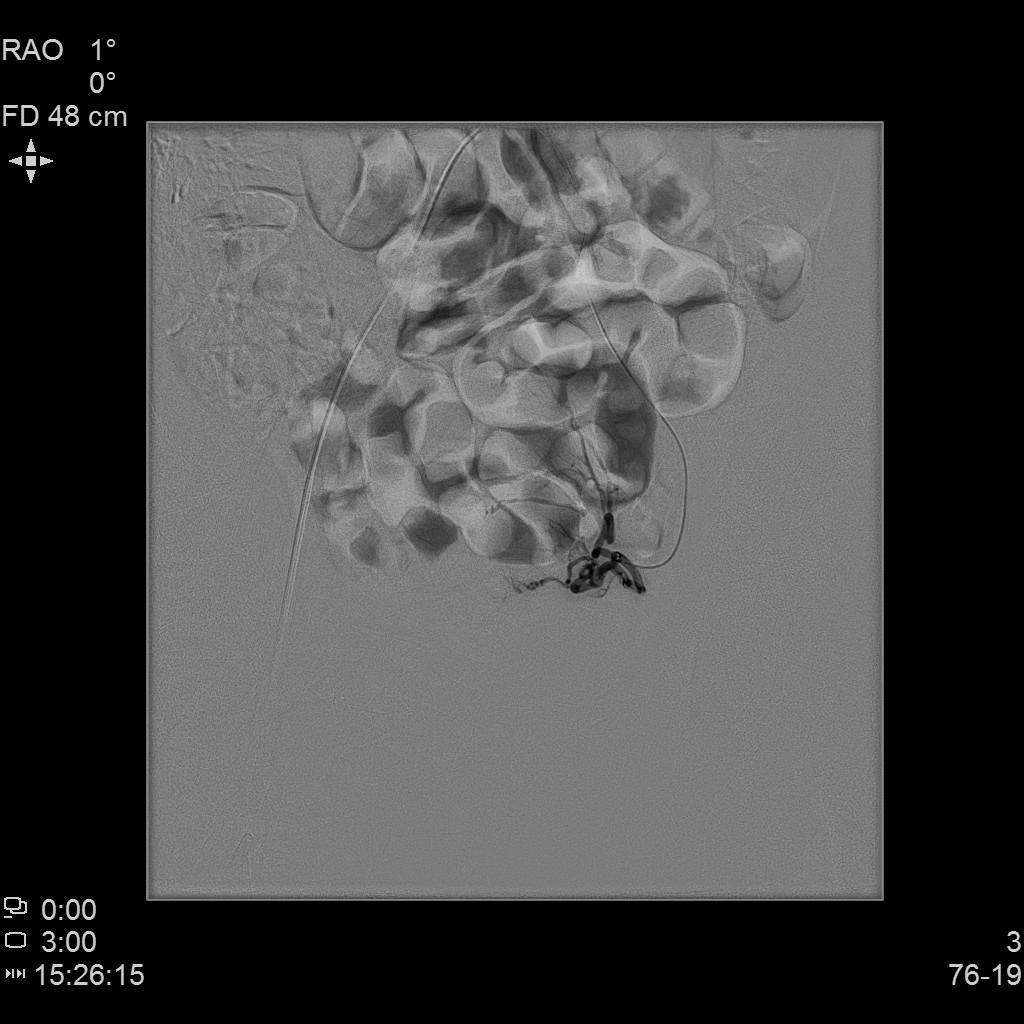

例2

中年患者,患有“子宫腺肌瘤”7年余,长期受痛经、月经量增多折磨,严重影响生活质量。经多处求医,经历药物调理、“曼月乐”宫腔植入、“海扶刀”消融术等多种治疗,痛经、月经量多等情况一直无法得到有效缓解,病情日益严重。

- 术前MRI检查显示子宫明显增大。

术前MRI检查显示子宫明显增大

- 插管至右侧子宫动脉,显示子宫右侧病灶情况

右侧子宫动脉造影

左侧子宫动脉造影

术后复查MRI显示子宫明显缩小,腺肌瘤明显坏死吸收